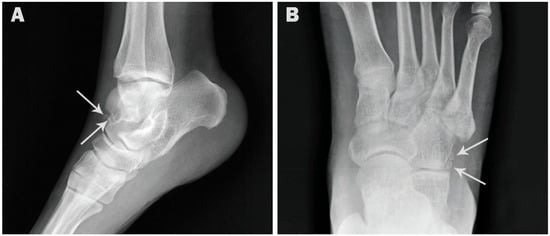

| Os trigonum | 154 (15.4) | 65 (13.0) | 89 (17.8) | 105 (15.6) | 49 (15.0) |

| p value | 0.0436 * | 0.8522 ns | |||

| Accessory navicular | 137 (13.7) | 77 (15.4) | 60 (12.0) | 99 (14.7) | 38 (11.7) |

| p value | 0.1410 ns | 0.2033 ns | |||

| Os peroneum | 115 (11.5) | 64 (12.8) | 51 (10.2) | 81 (12.0) | 34 (10.4) |

| p value | 0.2341 ns | 0.5260 ns | |||